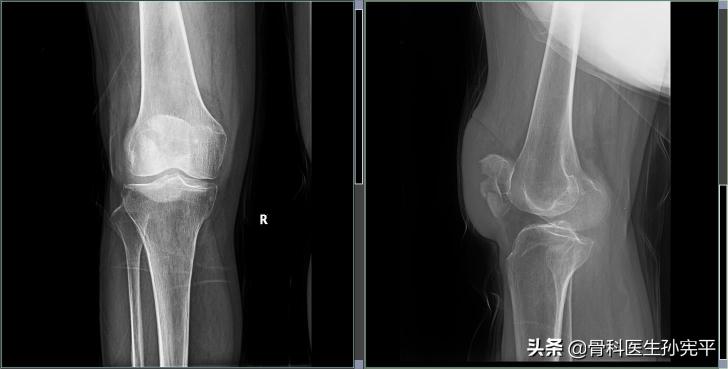

77岁老年女性,户外行走时摔伤,导致的右髌骨及左桡骨远端骨折伴尺骨茎突骨折

右髌骨骨折

髌骨骨折手术指征:因髌骨骨折是关节内骨折,关节面出现台阶或塌陷超过2mm、伸膝完整性破坏(不能抗重力伸膝)、骨折间隙大于2mm时均需手术治疗。